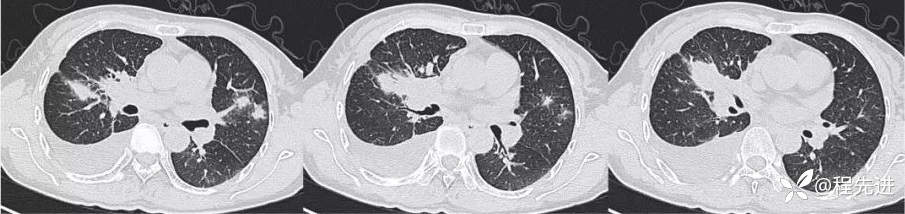

CT平扫:

肺窗